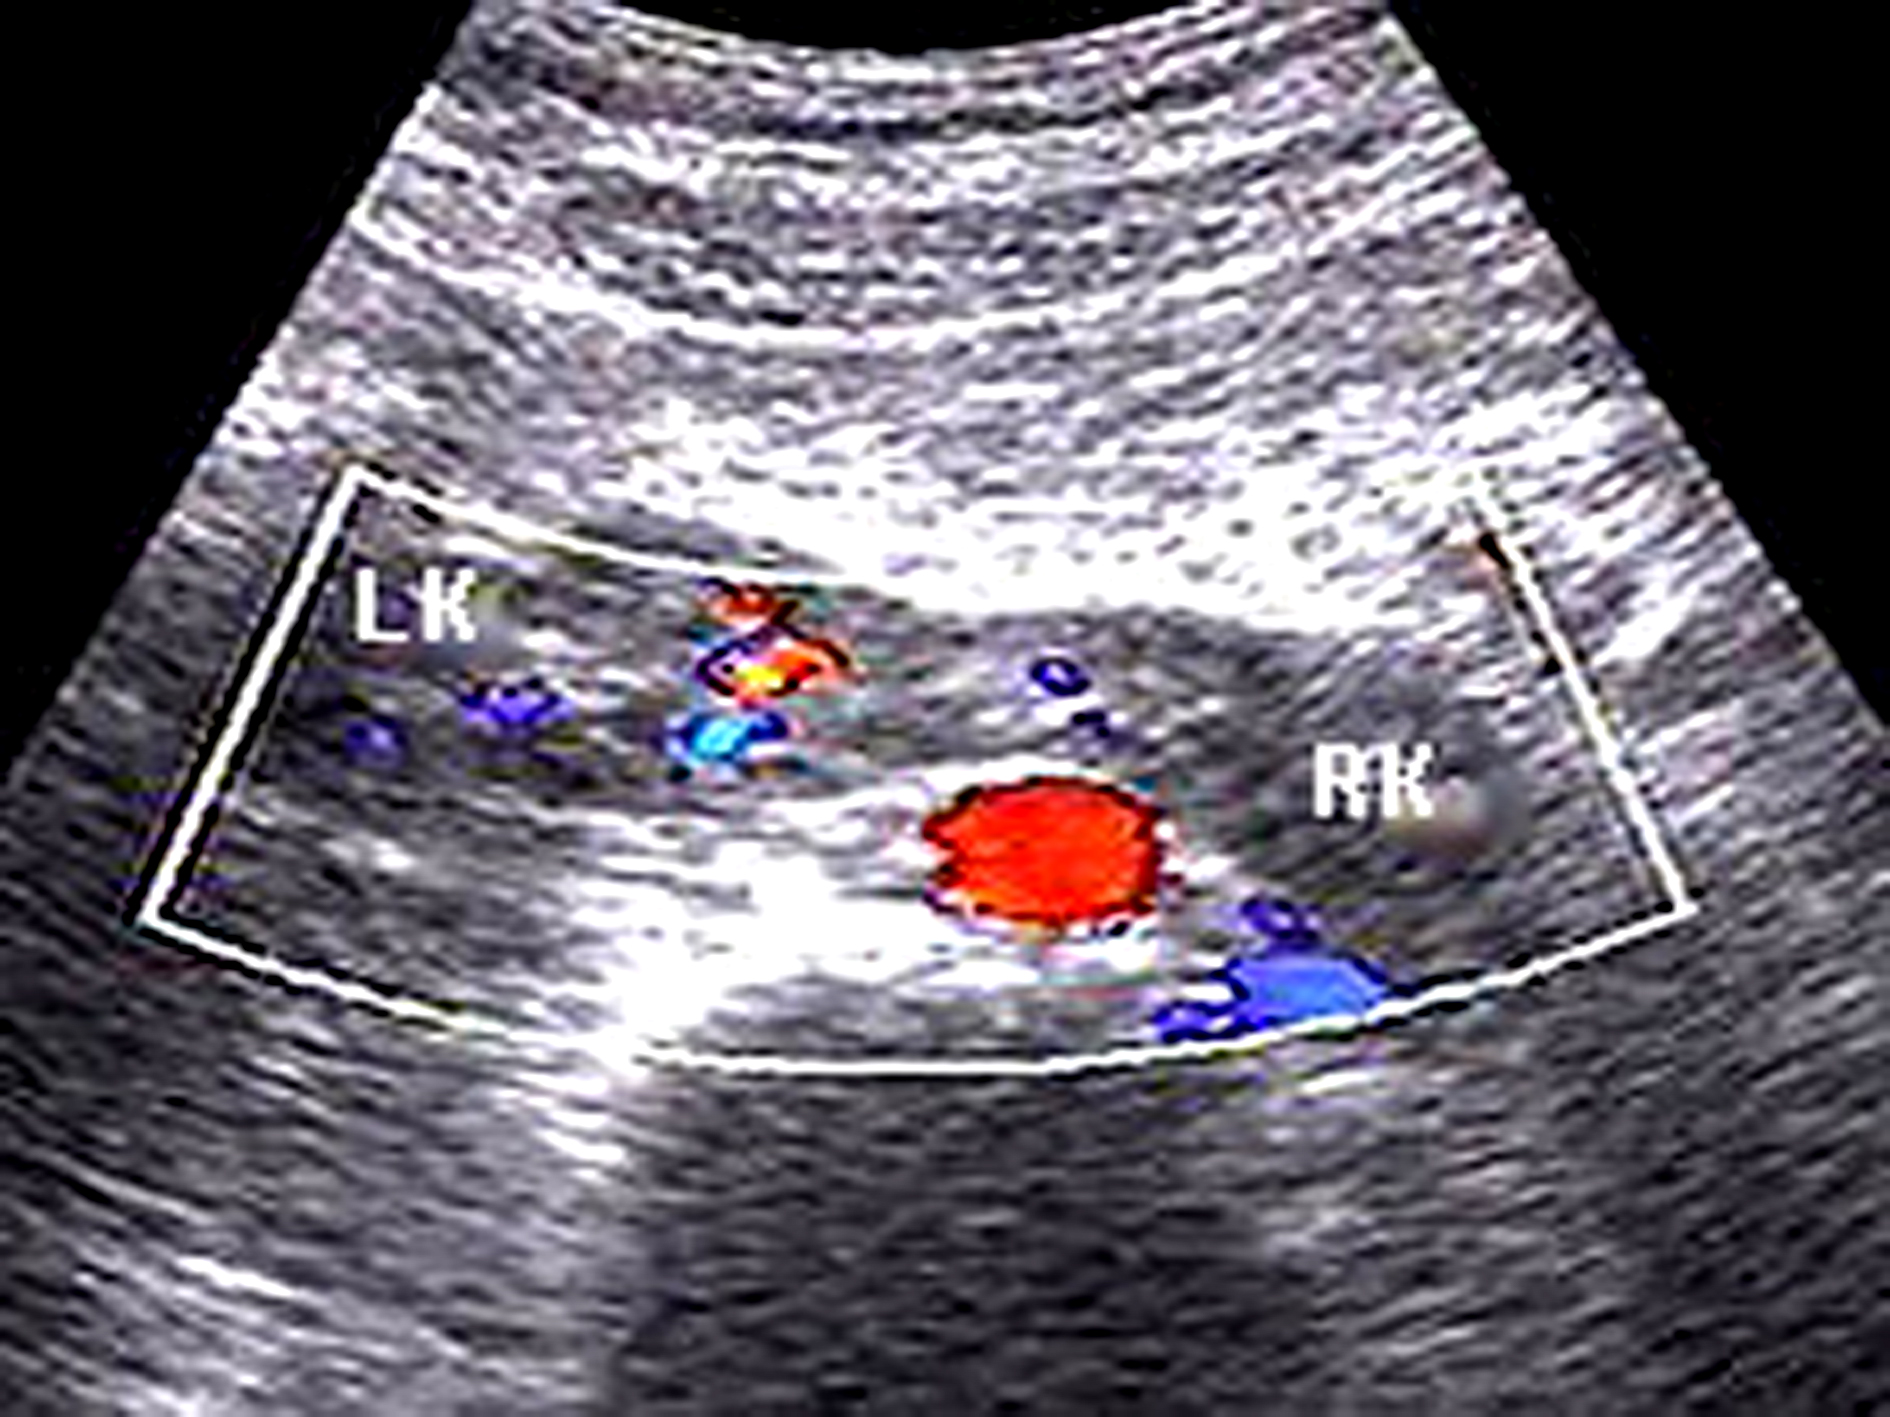

胎儿重复肾的超声诊断标准:①肾上部有偏向一侧的肾盂积水; ②输尿管囊肿;③输尿管扩张。有这三点特征性表现即可诊断(图3)。输尿管囊肿是输尿管入膀胱段黏膜下的囊状扩张,其位置低于胎儿膀胱或接近于尿道,使超声难以观察到。这是因膀胱空虚,误认输尿管疝为膀胱(假阴性),而膀胱充盈时的压迫可使输尿管疝暂时消除。重复肾的输尿管扩张,既与发育异常的肾和(或)输尿管有关,也与输尿管疝有关。有合并症状时需与尿路梗阻鉴别。

图3 A:孕24周。肾盂扩张(*);B:肾脏下方显示双输尿管扩张(箭头)